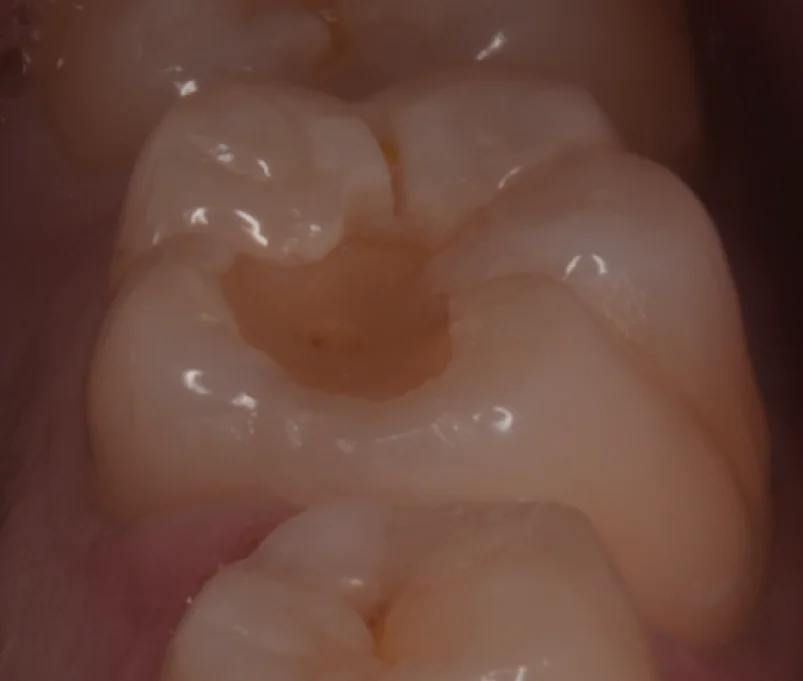

まずは術前からです。

画面上で右側に見える大きな奥歯が今回の治療部位になります。

親御さんに小さい頃に治療していただいたとのことでした。

角度を変えたのがこちらです。

その頃のレジンなのでやはり物性が悪く随分とすり減っていましたね。

こちらを除去していくと・・・